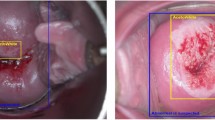

Digital colposcopy

All women underwent digital colposcopic assessment (Digital Video Colposcope SLC-2000, Shenzhen Goldway Industrial Inc., Shenzhen, China) as a primary screening test, performed by assessing abnormal areas after application of acetic acid (Sellors and Sankaranarayanan, 2003). Observations were recorded by quadrant.

Figure 1 shows the comparison of screening test performance among women aged 39 years or younger and 40 years or older, based upon corrected estimates. Visual inspection with acetic acid was significantly more sensitive in women aged 39 years or younger (49.9%) than older women (12.2%; χ12=7.51; P=0.006). Also colposcopy was slightly more sensitive, whereas LBC⩾ASCUS, HC2 and their combinations were slightly less sensitive in younger than older women, although none of these differences were statistically significant.

Colposcopy performed only moderately well as a primary screening test in our study, in agreement with suggestions from recent work (Jeronimo and Schiffman, 2006; Pretorius et al, 2007). Overall, sensitivity and specificity were only 54 and 85% respectively, which was similar to that in an earlier large study in China (Pretorius et al, 2007). Like VIA, colposcopy missed more than half of all CIN2+ among women aged 40 years or older. Colposcopy was substantially less sensitive than LBC or HC2, as in earlier studies with minimal verification bias (Belinson et al, 2001; Pretorius et al, 2007). The performance of visual methods appeared similar when analyses were restricted to CIN3.